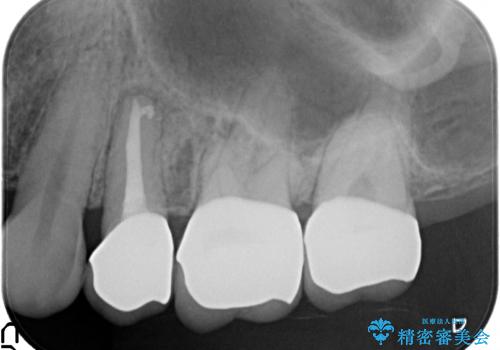

左上5は再根管治療を行い症状の緩解を確認後、オールセラミッククラウンによる補綴を行いました。

左上6、7番目の歯もしみるとのことだったので古い樹脂及び虫歯を除去後、オールセラミッククラウンによる補綴を行いました。

今回用いたオールセラミッククラウンはジルコニアフレームという白い素材の上にセラミックを盛っているため、審美性が非常に高いのが特徴です。

また、ジルコニアは人工ダイヤモンドの材料にも使われているほど高い強度を持っており、そのためオールセラミッククラウンは審美性だけでなく、奥歯やブリッジの補綴も可能とするクラウンです。